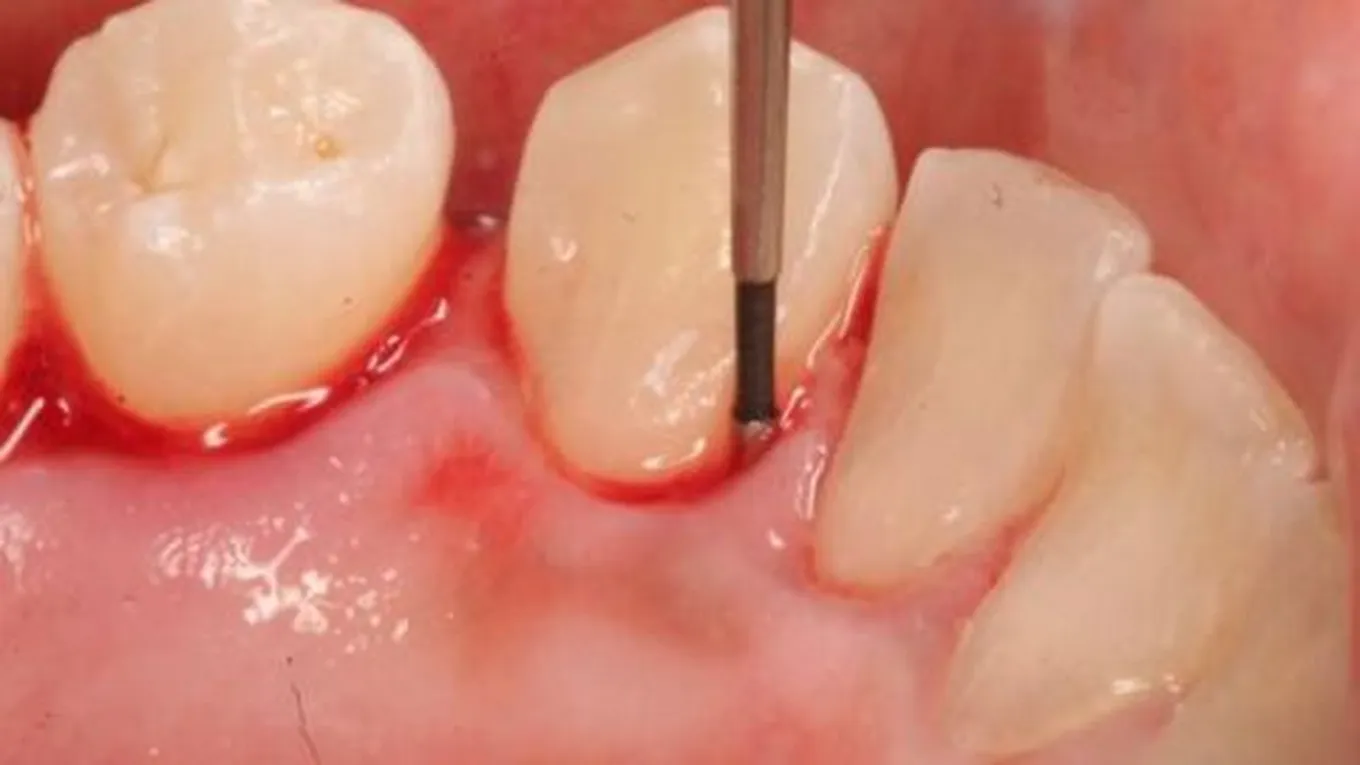

نزيف اللثة اثناء الحمل

اثناء الحمل يرتفع مستوى هرمون الاستروجين الذي يسبب تورم اللثة وجعلها اكثر ليونة على الاحوال العادية ويزيد من توارد الدم الى اللثة وهذا يجعلها معرضة اكثر لحدوث

اثناء الحمل يرتفع مستوى هرمون الاستروجين الذي يسبب تورم اللثة وجعلها اكثر ليونة على الاحوال العادية ويزيد من توارد الدم الى اللثة وهذا يجعلها معرضة اكثر لحدوث النزيف والعدوى خصوصا مع عدم العناية الصحية بالفم